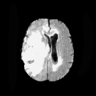

The Flair experiment results are obtained using a training of two cycles in the first stage and four cycles in the second stage to reach the peak separation, and the threshold value is taken at the intensity of 170. For T2 we use two cycles in the first stage and two cycles in the second stage, and the threshold is taken at 220. Both thresholds are taken based on the rightmost peaks of the histograms of reconstructed images. We obtain a subject-wise mean dice score of 79.89% on the Flair scans and 88.57% on the T2 scans. Despite the lower score compared to T2, the Flair modality provides the potential of identifying additional anomalies, which may not be limited to HGG or LGG, as shown in the third column of Fig. 6. However, since the focus of this experiment is to segment HGG and LGG only, using the T2 modality outperforms the Flair in term of the Dice scores as reported in Table 2, and the predicted masks as shown in Fig. 6. Aside from that, on the Flair scans our method suffers both under- and over-segmentation as shown in Fig. 7 and struggles to segment tumors using one uniform threshold as shown in Fig. 8. Typically, we use the rightmost peak as the threshold for brighter tumors; however, the peaks separating tumors in these cases of Fig. 8 occur as the leftmost peak. Such flip further lowers the segmentation score, even though the algorithm is able to separate the anomaly as one of the two cuts.

Although our method has consistently better performance of segmenting brain tumors on T2, as shown from Fig. 6 to Fig. 8. In the case of T2, the primary disadvantages occur due to the inclusion of other regions, such as Cerebrospinal Fluid (CSF), eyeballs, etc., which appear dark in the Flair modality. In order to alleviate these false positives on T2 scans, we multiply the predicted masks with the Flair input images. Then we re-calibrate the output by taking a threshold at the intensity of 50 (roughly 0.2 in the range [0,1]) to generate our final mask. This post-processing is our new choice for the private dataset. We did not use the erosion/dilation operation because it is more efficient for cases with discontinuous segmentation results, which is the one our public datasets suffer with, as shown in Fig. 4, but not our private dataset. This new post-processing improves the performance to a patient-wise mean dice score of 91.58% on T2 scans with two-fold cross validation.